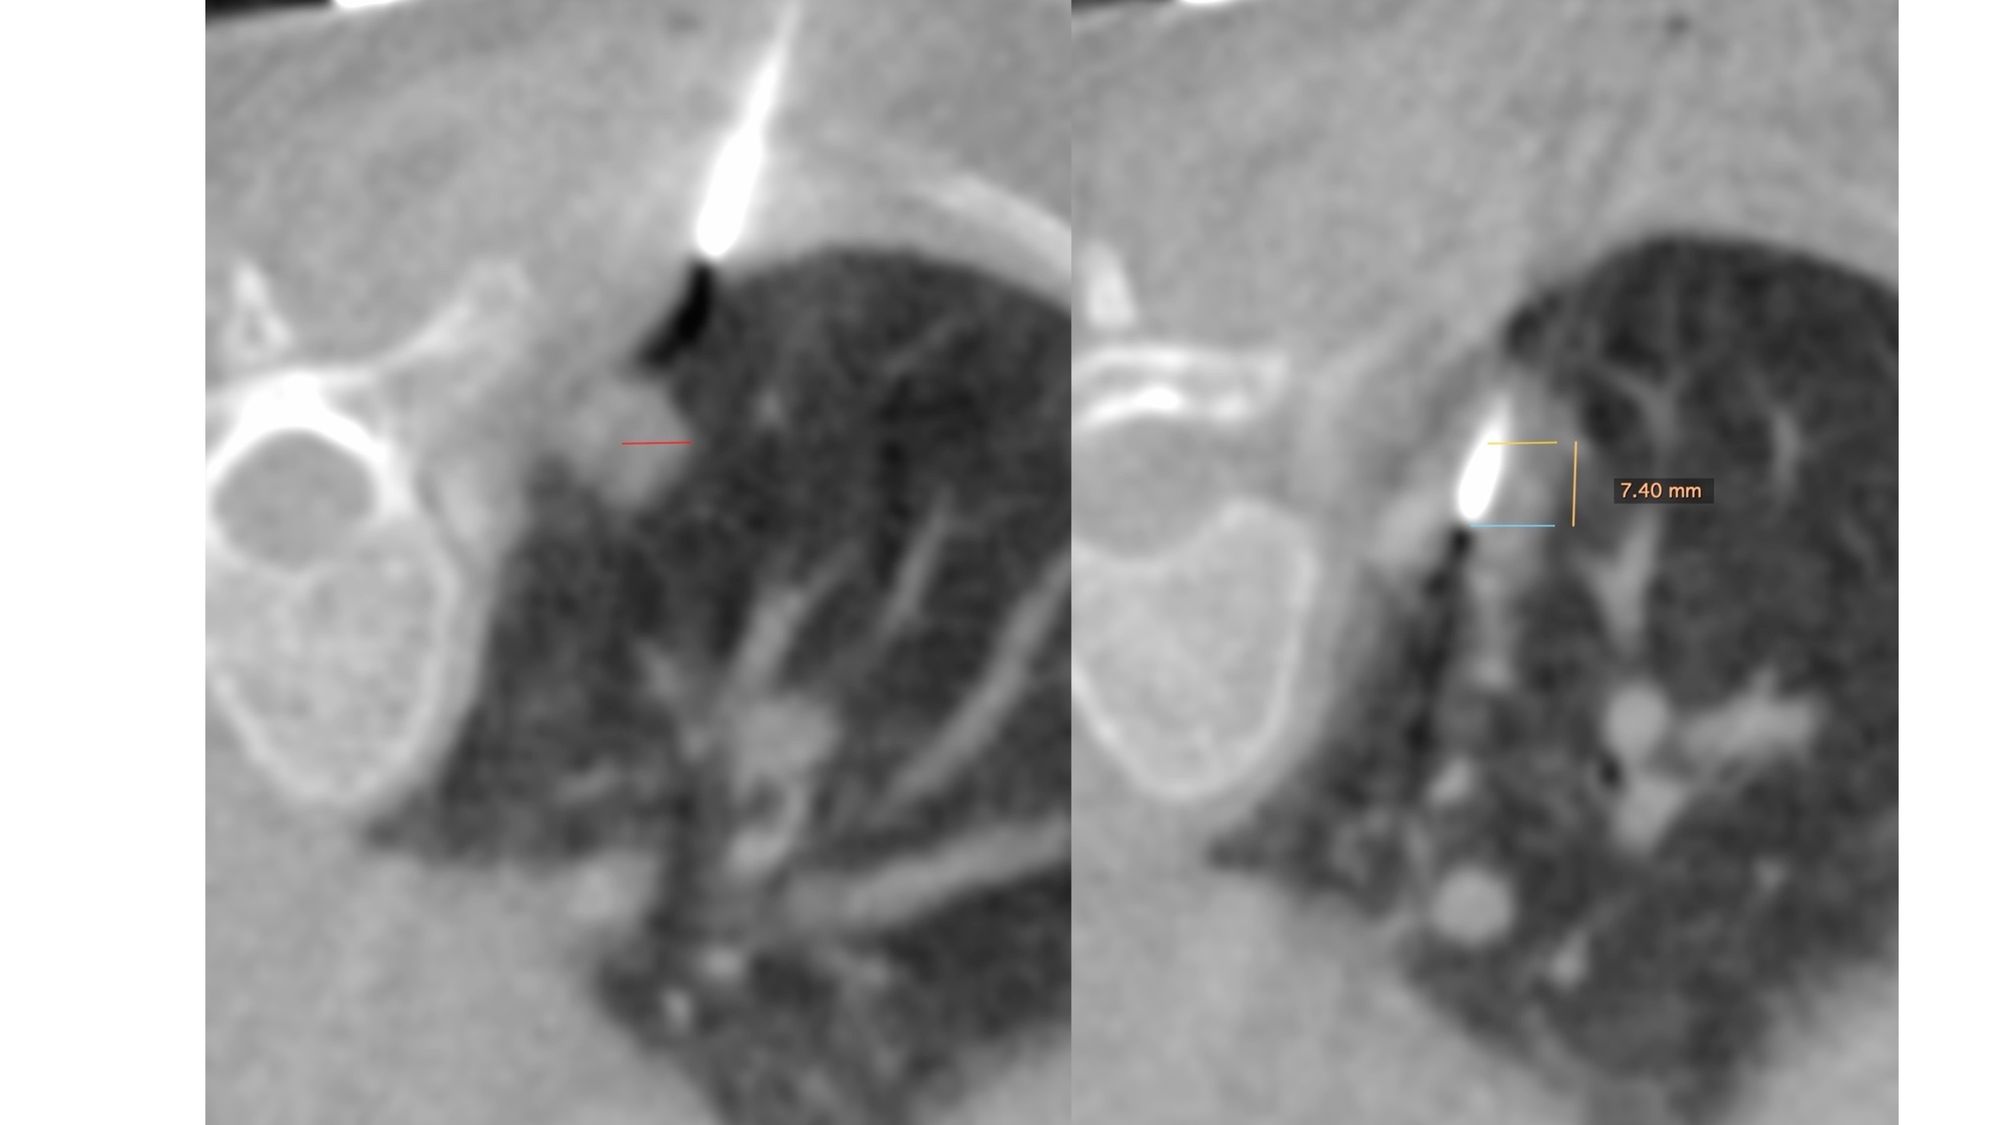

Case 35: Spearing a Moving Lung Nodule

Bhavin Jankharia - 21 May 2021